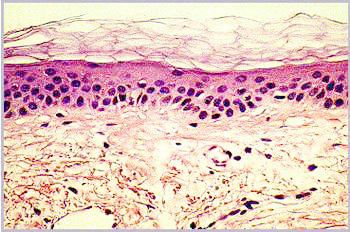

Aged skin can be recognized immediately by the presence of wrinkles, flaccidity and actinic keratosis. A histological section reveals some of the causes of these symptoms of ageing (Fig. 1 a and b).

Fig. 1a: Microscopic sections through the skin of a 21-year-old

Fig. 1b: Microscopic sections through the skin of a 66-year-old

Fig. 1 a and b

Microscopic sections through the skin of a 21-year-old and a 66-year-old

In young skin, the lower part of the skin, the dermis, has a very regular structure. This regularity is no longer so clear-cut in older skin. The dermis contains irregular structures and flaws and appears less compact. The next highest layer, the epidermis, is somewhat thinner in older skin than in younger. More noticeable than this slight change in the thickness of the epidermis, however, is the disappearance of the curvature of the epidermal-dermal interface. In older skin this interface is flat, so that the cohesion between dermis and epidermis is weaker. Finally, in the upper layer, the stratum corneum, scarcely any differences can be observed under the microscope.